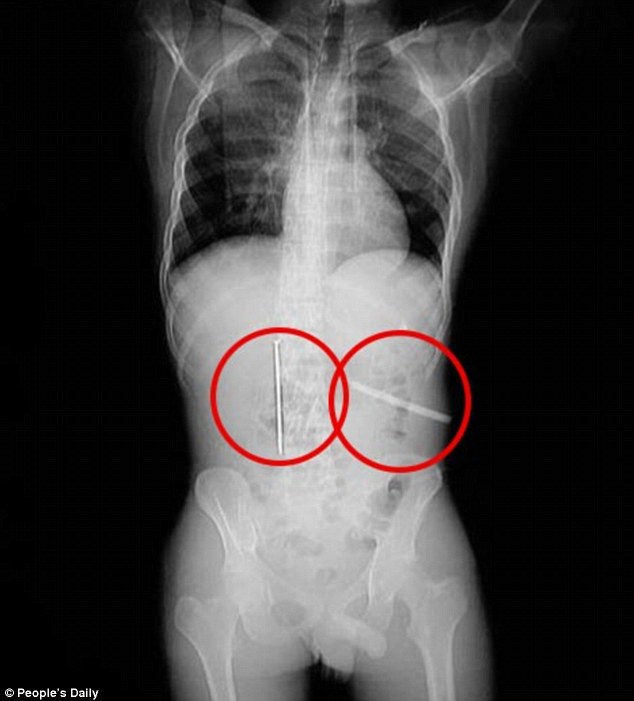

Chiếc đinh dài 13cm và hình ảnh lưỡi cưa trong bụng bệnh nhân. Ảnh: Daily Mail |

Anh đã thách người đàn ông nuốt đinh dài 13 cm, đường kính 6mm, số tiền nhận được sẽ là 2000 tệ (khoảng 7 triệu đồng).

Nếu nuốt lưỡi cưa dài 12cm, rộng bằng ngón tay trỏ sẽ được 4000 tệ (khoảng 14 triệu đồng).Xiao Gong đã bất chấp sự nguy hiểm đến tính mạng mà nuốt cả cây đinh dài gần 13cm và lưỡi dao răng cưa để nhận được số tiền trên.